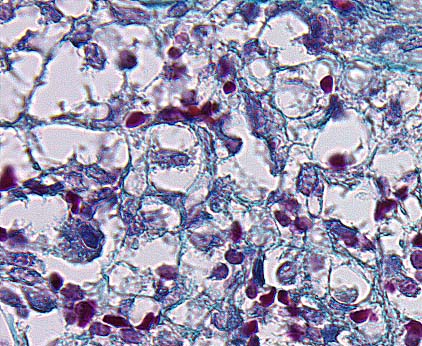

Return To Cartoon of Spleen